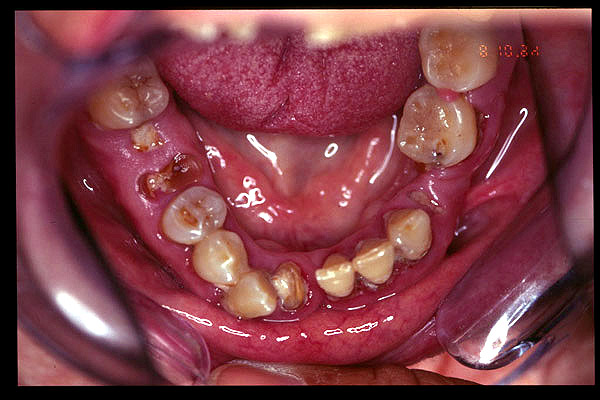

CM Edentulismo parcial, restos radiculares, caries y placa bacteriana